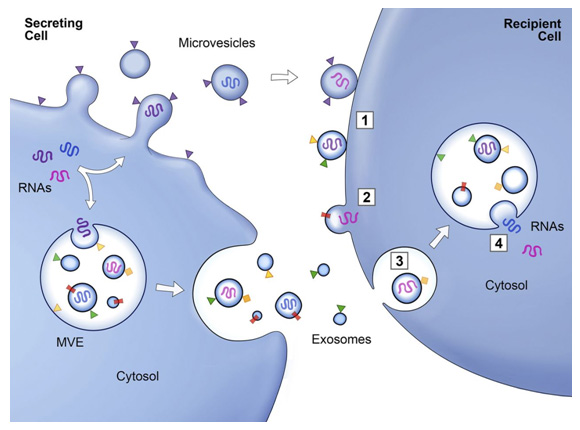

細胞外囊泡 (EV) 是膜結合載體,可分為三種類型,包括外泌體、微囊泡 (MV) 和凋亡小體。作為一種重要的 EV,外泌體在過去十年中受到了最多的關注。外泌體可以由各種細胞分泌,并通過其內容物(包括脂質、核酸和蛋白質)介導細胞間通訊。

外泌體的直徑通常在30-150 nm之間,密度在1.13-1.19 g·mL-1.19之間。發現脫落的膜囊泡可能具有生理功能,并建議將這些囊泡作為外泌體。1983 年,Harding 等人,觀察到膜結合囊泡可以通過多囊泡內體 (MVE) 胞吐作用釋放。1987 年,Johnstone 等人,觀察到網織紅細胞成熟過程中的外泌體釋放與質膜活性有關。2007 年,Valadi 等人。發現 mRNA 和 microRNA 可以通過外泌體發送到其他細胞,表明外泌體可能通過遞送核酸來介導細胞間通訊。此后,越來越多的研究表明外泌體通過介導細胞間通訊發揮重要的生理和病理作用。

外泌體的產生過程